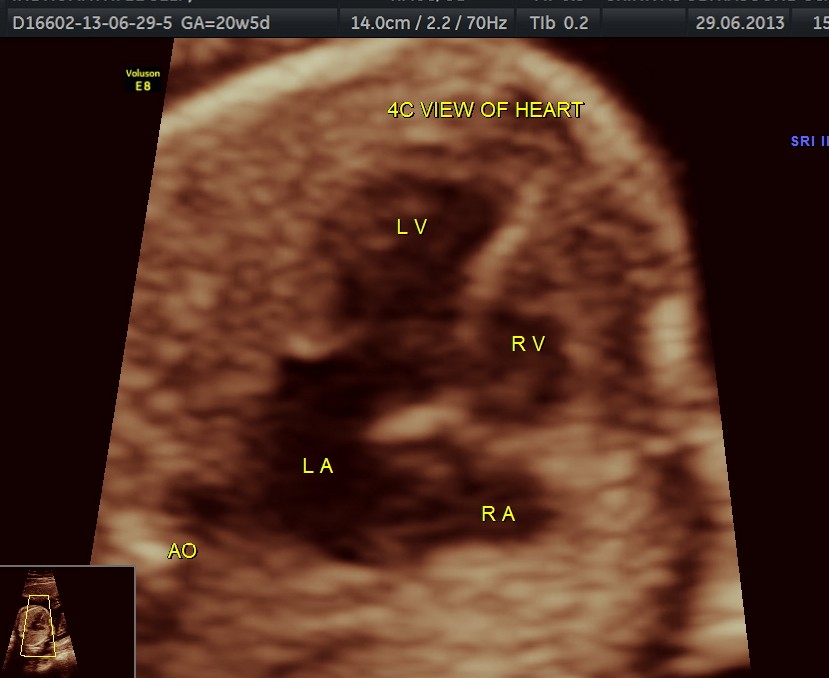

The following pictures are of the 20 weeks gestation.

The 4 chamber view shows the patent foramen ovale. 2 pulmonary veins are also seen entering the left atrium.